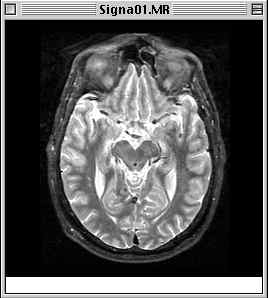

The image you select will open immediately. If you were to open Signa01.MR, for example, you should get a window which looks something like this:

View Image display of Signa01.MR